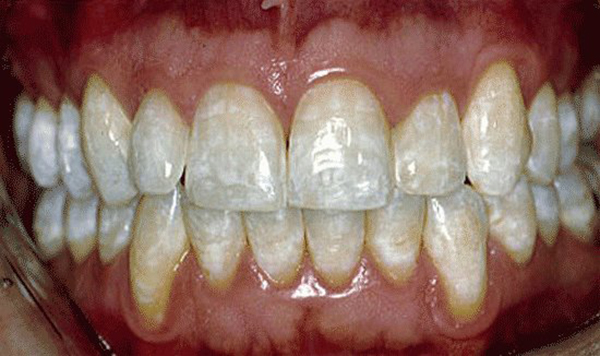

- Пятнистая: на поверхности образуются пятна сероватого или беловатого цвета. Пятна могут сливаться и образовывать одно большое. Поверхность гладкая и блестящая, отсутствуют чёткие границы, они плавно переходят в здоровые участки.

Пятнистая. Появление множества пятен, без полосок, гладкая эмаль рядом с пятном.